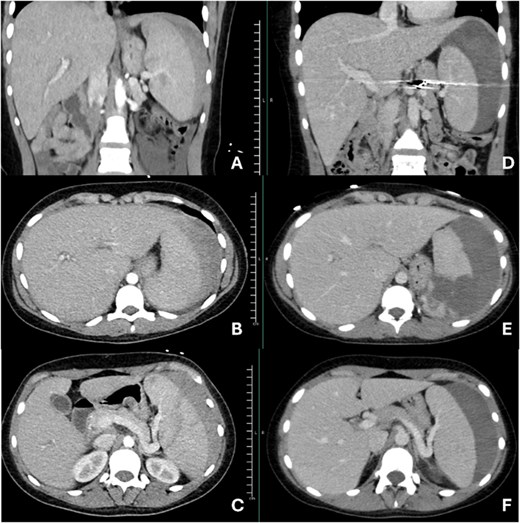

The patient’s complete blood count test revealed a low hemoglobin level and normal white blood cell count. The liver function test reported within a normal range for liver enzymes; however, she tested positive for infectious mononucleosis with a monospot test. The computed tomography (CT) with contrast from outlying facility revealed an American Association for the Surgery of Trauma (AAST) score of grade 3 splenic injury with hemoperitoneum (Fig. 1A–C). This prompted transfer to the level one trauma center.

Images A, B, and C are representations of initial imaging prior to splenic artery embolization. Images D, E, and F are images taken at her second admission, 12 days after splenic artery embolization. Images D and F show continued flow through the splenic artery.

Unfortunately, she returned to the same outlying facility nine days after discharging due to increasing pain, lethargy, and the inability to tolerate a diet. Workup revealed continued left upper quadrant abdominal pain, a low hemoglobin level, and stable vital signs. She continued to have low-grade fevers thought to be secondary to mononucleosis infection. New CT abdomen/pelvis with IV contrast imaging revealed a significant increase in the patient’s perisplenic hematoma (AAST grade 4 injury) with continued flow through the splenic artery (Fig. 1D–F), which led the surgical team to proceed with an open splenectomy.